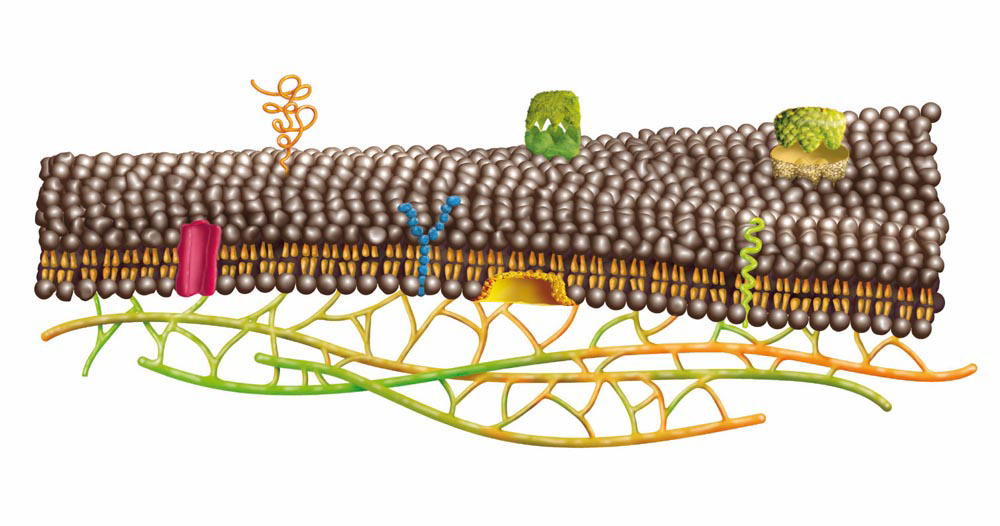

Herzlich willkommen! Ich bin Ihre Expertin für medizinische Illustrationen und kreative Kinderbuch-Illustrationen. Mit einem Auge für wissenschaftliche Genauigkeit und einer Liebe zur Gestaltung kindgerechter Erzählwelten schaffe ich Bilder, die informieren und begeistern. Entdecken Sie mein Portfolio und lassen Sie sich von meiner Arbeit überzeugen!